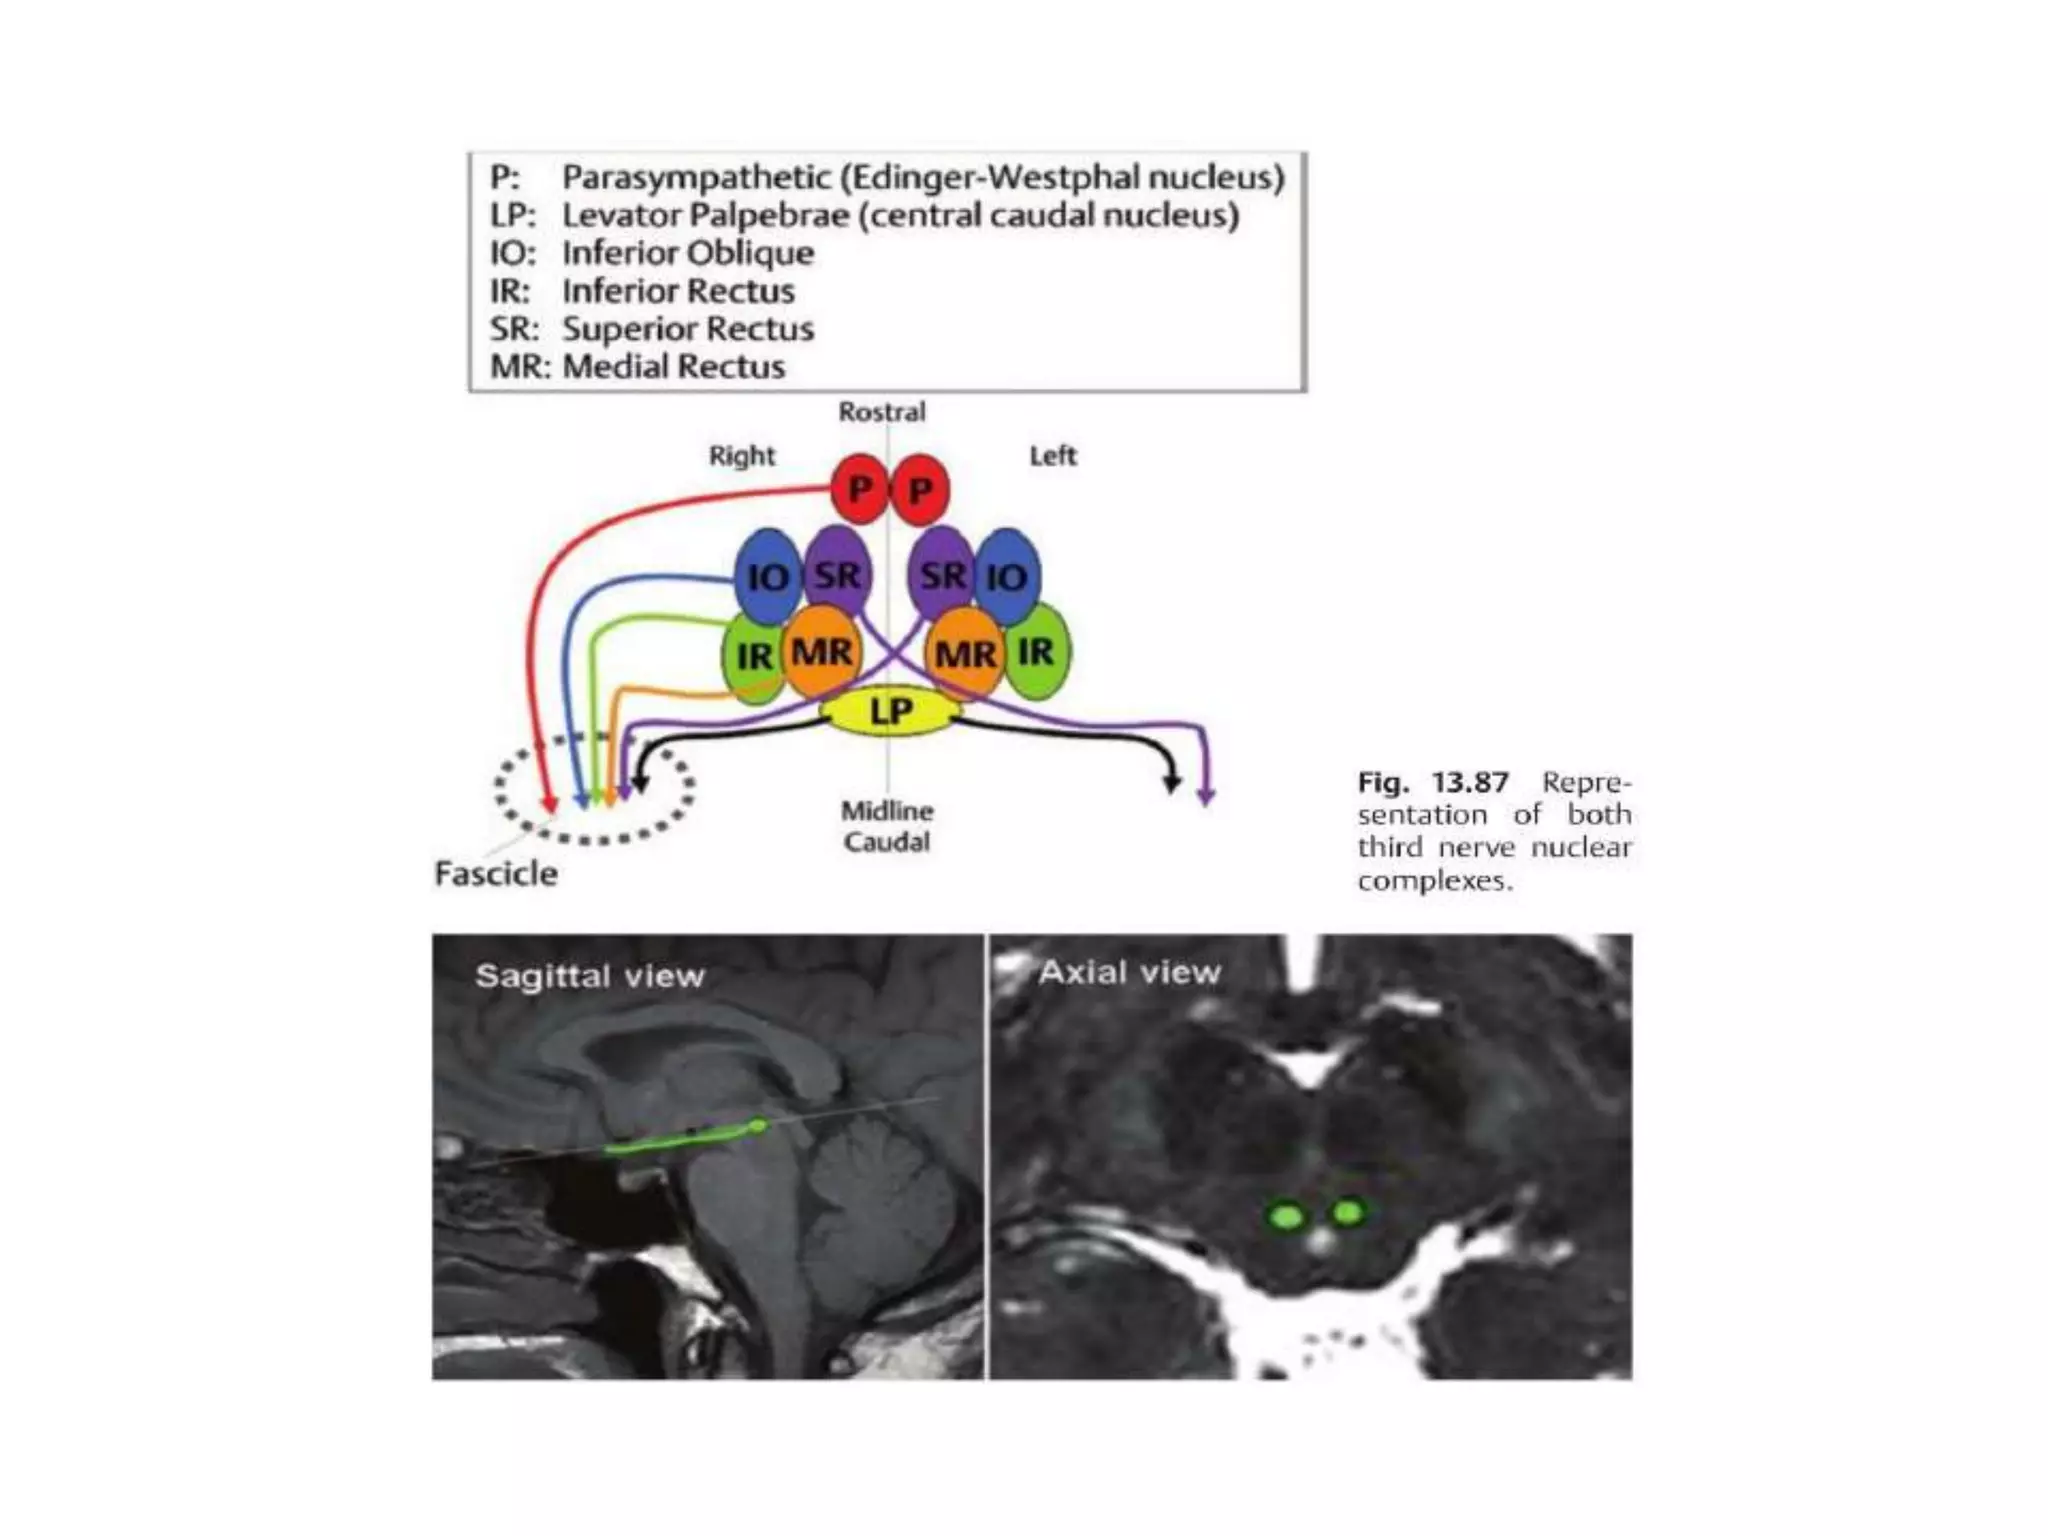

3rd n. anatomy

• Complex of subnuclei(dorsal of midbrain) –>subarachnoid space-

>sup. Cerebral a. and post. Cerebral a.-> cavernous sinus->sup.

orbital fissure, annulus of zinn->sup. division(levator, SR), inf.

Division(parasym,MR,IR,IO)

3rd n. anatomy •Complex of subnuclei(dorsal of midbrain) –>subarachnoid space- >sup. Cerebral a. and post. Cerebral a.-> cavernous sinus->sup. orbital fissure, annulus of zinn->sup. division(levator, SR), inf. Division(parasym,MR,IR,IO)